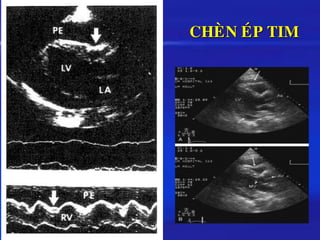

❖ SIEÂU AÂM

Khoaûng troáng echo (+)

➢ TD löôïng lôùn: tim du ñöa töï do trong khoang MNT

Naëng: möùc ñoä chuyeån ñoäng thay ñoåi,  keát hôïp so le

ñieän theá

➢ Cheøn eùp tim:

– Xeïp nhó P , thaát P thì taâm tröông

– HV: thaát P taêng, thaát T giaûm, loå môû van 2 laù 

Ñoâi khi thaát P , chuyeån ñoäng vaøo trong cuoái taâm tröông

cuûa vaùch töï do thaát P, nhó P

CHEØN EÙP TIM

◼ Dòch MNT -> taéc ngheõn doøng maùu ñoå veà thaát